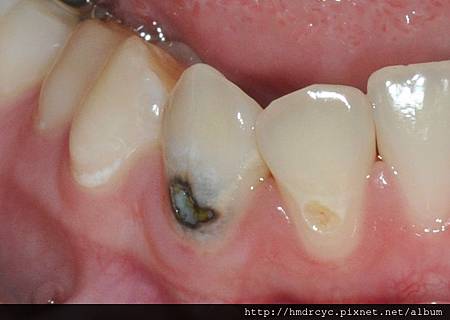

根管發炎的膿包大部分是可以拔除的

因為化膿的範圍受到限制

拔除後傷口可以清乾淨 唯一要小心就是

如果跟管發炎化膿跟牙周病連動

整個牙肉腫起來 那又跟牙周發炎一樣需先清潔吃藥等消腫